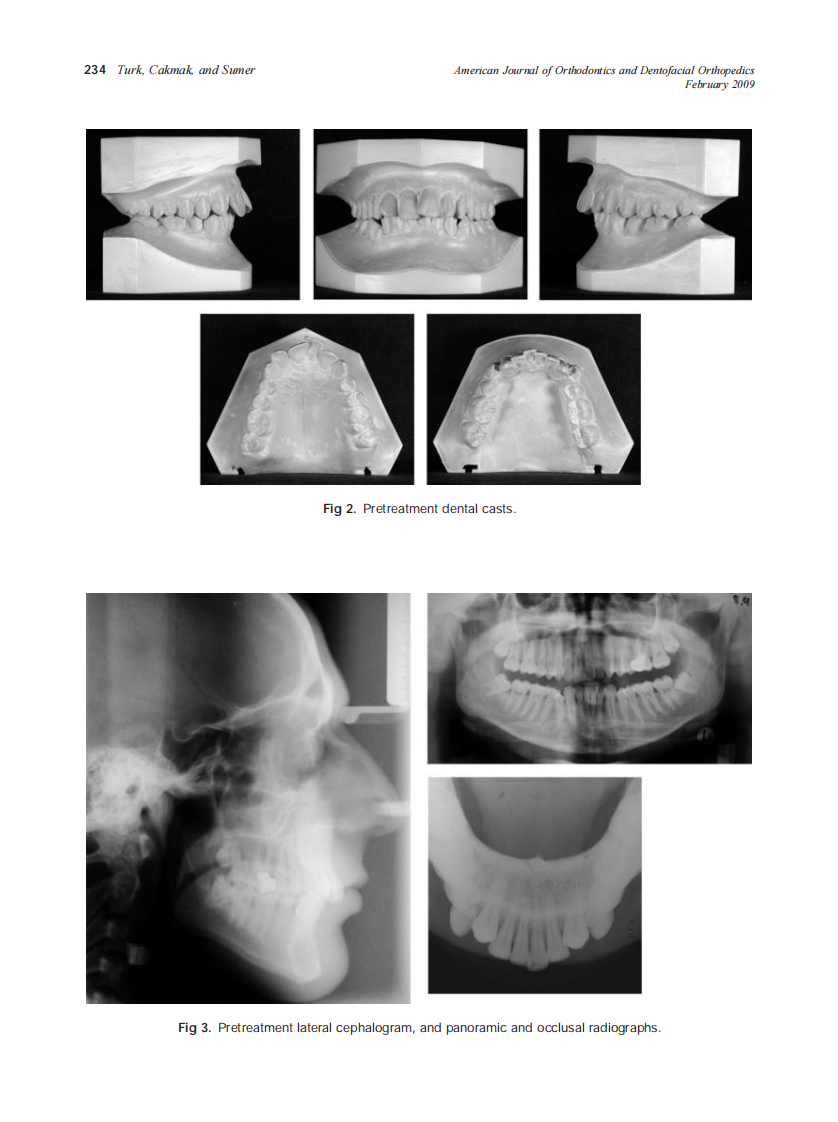

2009_135_2_232_240_Turk.pdf